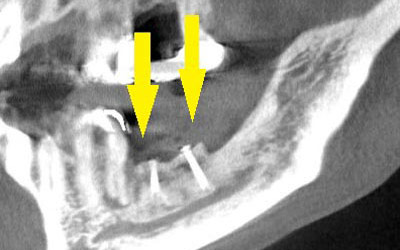

インプラントを埋入するために、骨を増やす方法はいくつかありましたが、この場合、患者様ご自身の骨をブロック状で移植するのが最も適していると判断し、自家骨移植術を行ないました。患者様ご自身の下顎前歯の下方から骨を採取して、骨がなかった部位に移植し、スクリューで固定したCT画像です。黄色矢印部分が、2つの骨片を移植して、固定したところです。

手術後の、別な方向からみたCT画像です。術前に大きく吸収されていた部分に、骨のブロックが移植され、骨が造成されています。真っ白にピンのように写るのは、骨を固定した小さなスクリューです。

移植した骨が周囲の骨と、結合したのを待ち、6か月後に、インプラント埋入手術を行いました。下の写真が、インプラント埋入後のCT画像で、黄色矢印に示すように、インプラントが2本埋入できました。

インプラント埋入後の、別な方向からみたCT画像です。神経の通る管にややギリギリでしたが、神経は傷つけずに、インプラントが埋入できました。この後、4か月ほどで、咬む歯の部分、上部構造を完成させました。